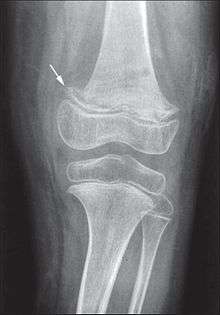

X-ray of the lower and upper limbs (arrow indicates scurvy line).

Ascorbic acid is needed for a variety of biosynthetic pathways, by accelerating hydroxylation and amidation reactions. In the synthesis of collagen, ascorbic acid is required as a cofactor for prolyl hydroxylase and lysyl hydroxylase. These two enzymes are responsible for the hydroxylation of the proline and lysine amino acids in collagen. Hydroxyproline and hydroxylysine are important for stabilizing collagen by cross-linking the propeptides in collagen. Defective collagen fibrillogenesis impairs wound healing. Collagen is an important part of bone, so bone formation is affected. Defective connective tissue leads to fragile capillaries, resulting in abnormal bleeding. Untreated scurvy is invariably fatal.[15]